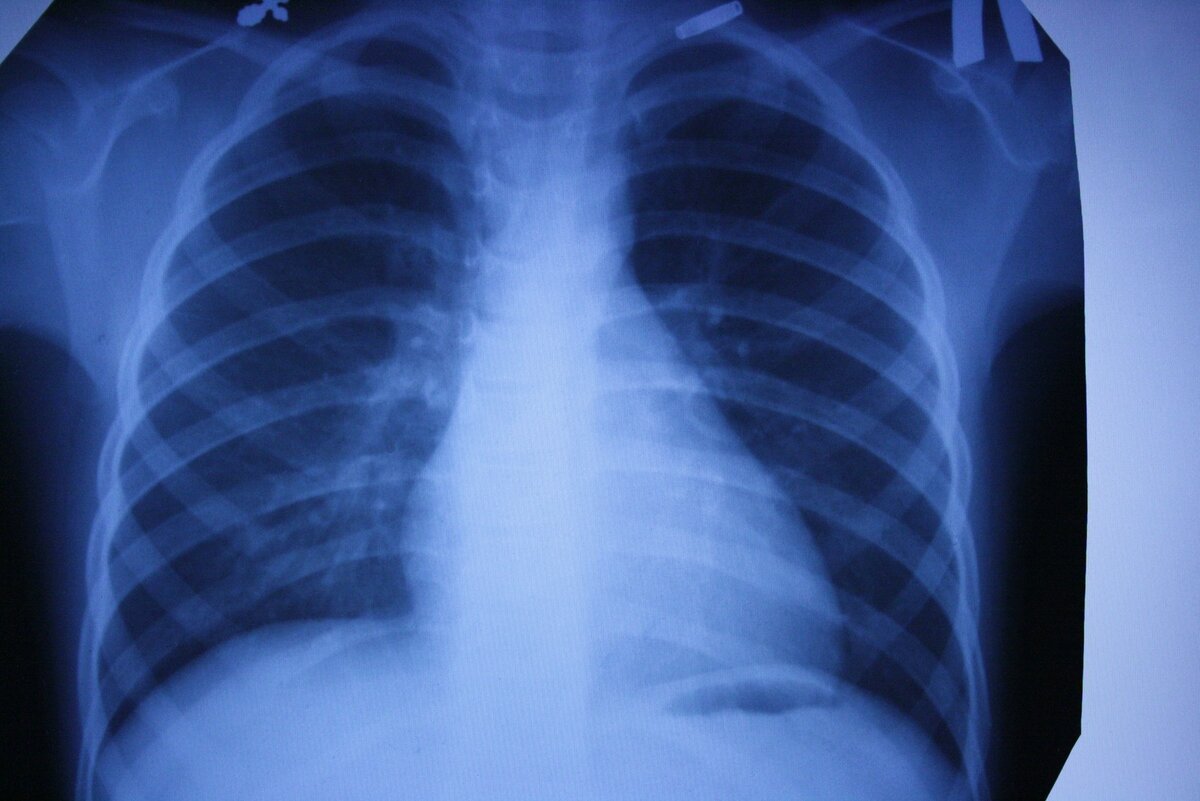

Коронавирус поражает легкие. Симптомы начинаются с лихорадки, сопровождаемой сухим кашлем, который может привести к проблемам с дыханием. По словам ученых, в среднем требуется пять дней, чтобы начать показывать симптомы, но у некоторых людей симптомы появляются гораздо позже Всемирная организация здравоохранения (ВОЗ) сообщает, что инкубационный период длится до 14 дней. Но некоторые исследователи говорят, что может быть до 24 дней.

Коронавирус поражает легкие. Симптомы начинаются с лихорадки, сопровождаемой сухим кашлем, который может привести к проблемам с дыханием.

коронавирус  поражает легкие